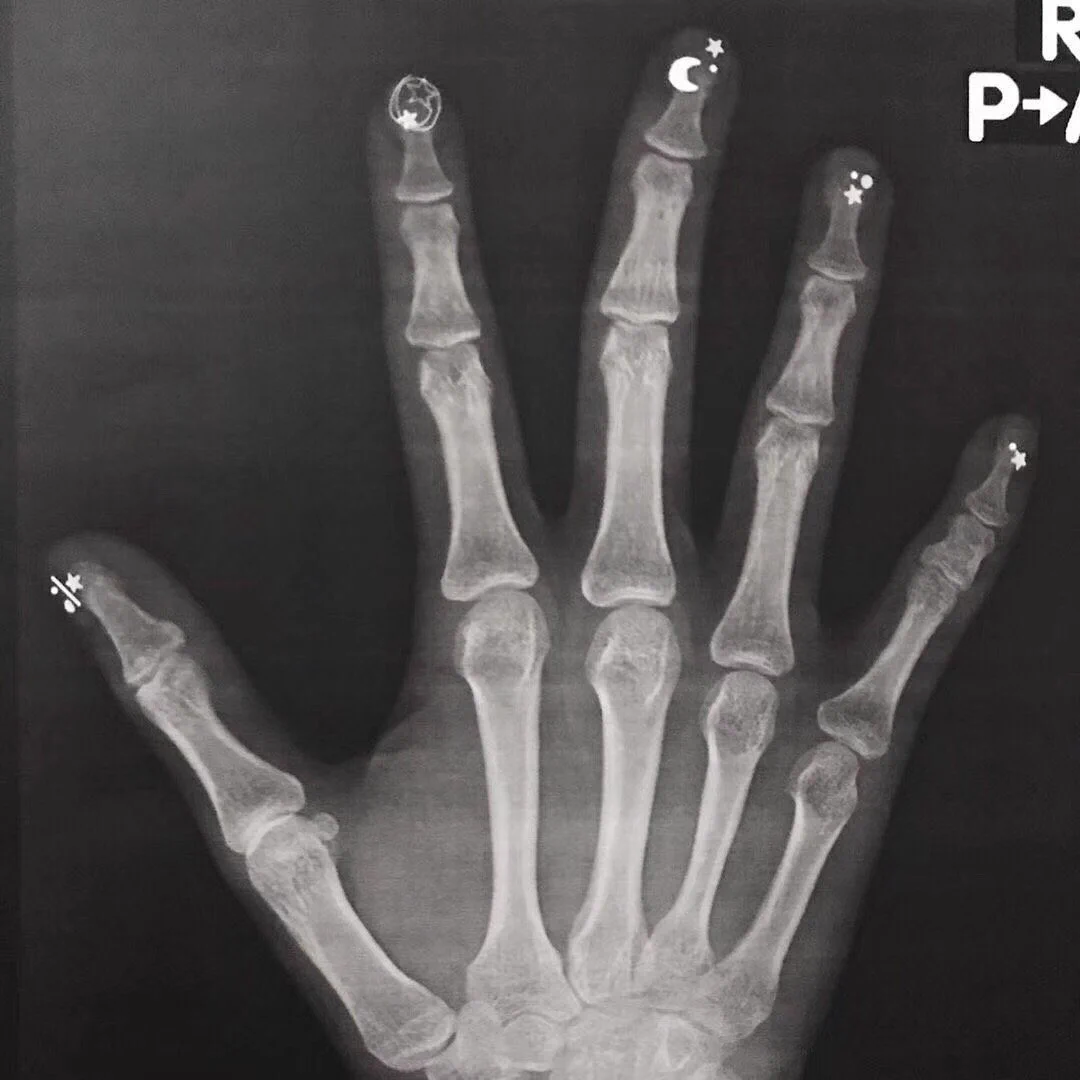

レントゲンを撮るとき、腕時計やアクセサリーなど、身に付けているものを外すように言われますよね。ただ、指先に施したネイルアートは、その場で簡単に取ることはできません。こちらのツイートでは、ネイルアートをしたままレントゲンを撮ったらどうなるのか、そのときの画像が紹介されていました!

ネイル付けたまま撮るとレントゲンがファンタジーになるから気をつけて

ネイルアートをしたままだと、このようにそのままレントゲン写真に写るんですね!

しかも、このときのアートが星や月の可愛い柄で、とってもファンタジー。

骨とのギャップがありすぎです。

お医者さんが診断するには支障がないレベルですが、見てびっくりされたかもしれませんね。

リプライ欄では、整形外科勤務の方も「こんなの見たことない」とコメントされていました。

手のレントゲンを撮る機会などなかなかありませんし、偶然撮れた貴重な一枚でした!